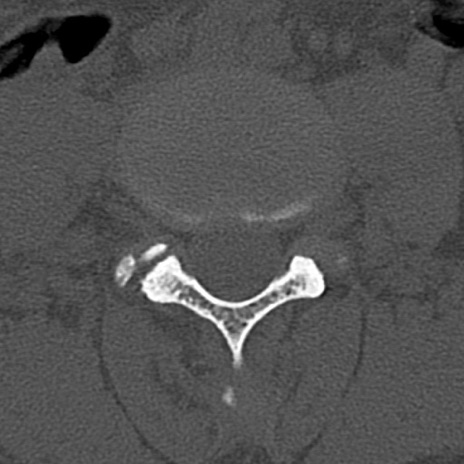

腰椎CT

横断像と矢状断像